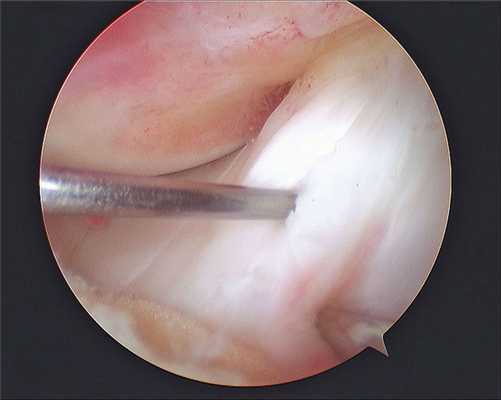

1. Артроскопическая частичная менискэктомия показана пациентам с дислоцированными или нестабильными повреждениями менисков, при которых не может быть выполнен шов мениска (например, повреждения в белой зоне, сегментарные или сложные разрывы менисков) и которые сопровождаются локальной болезненностью в соответствующей области суставной щели коленного сустава и механической симптоматикой, включающей щелчки, заклинивание или блокирование сустава

2. С морфологической точки зрения выделяют радиальные (рис. 1, А), горизонтальные (рис. 1, Б), вертикальные (или продольные, рис. 1, В), в виде «клюва попугая» (рис. 1, Г), «ручки лейки» (рис. 1, Д) и дегенеративные или комплексные разрывы менисков (различные плоскости разрыва, измененная ткань мениска, рис. 1, Е)

• Неадекватная визуализация или неправильная интерпретация комплексных разрывов менисков, особенно таких, которые включают сегментарный компонент или разрыв в виде «клюва попугая», может привести к тому, что выполненная резекция мениска окажется недостаточной, и болевой синдром или механические симптомы у пациента останутся